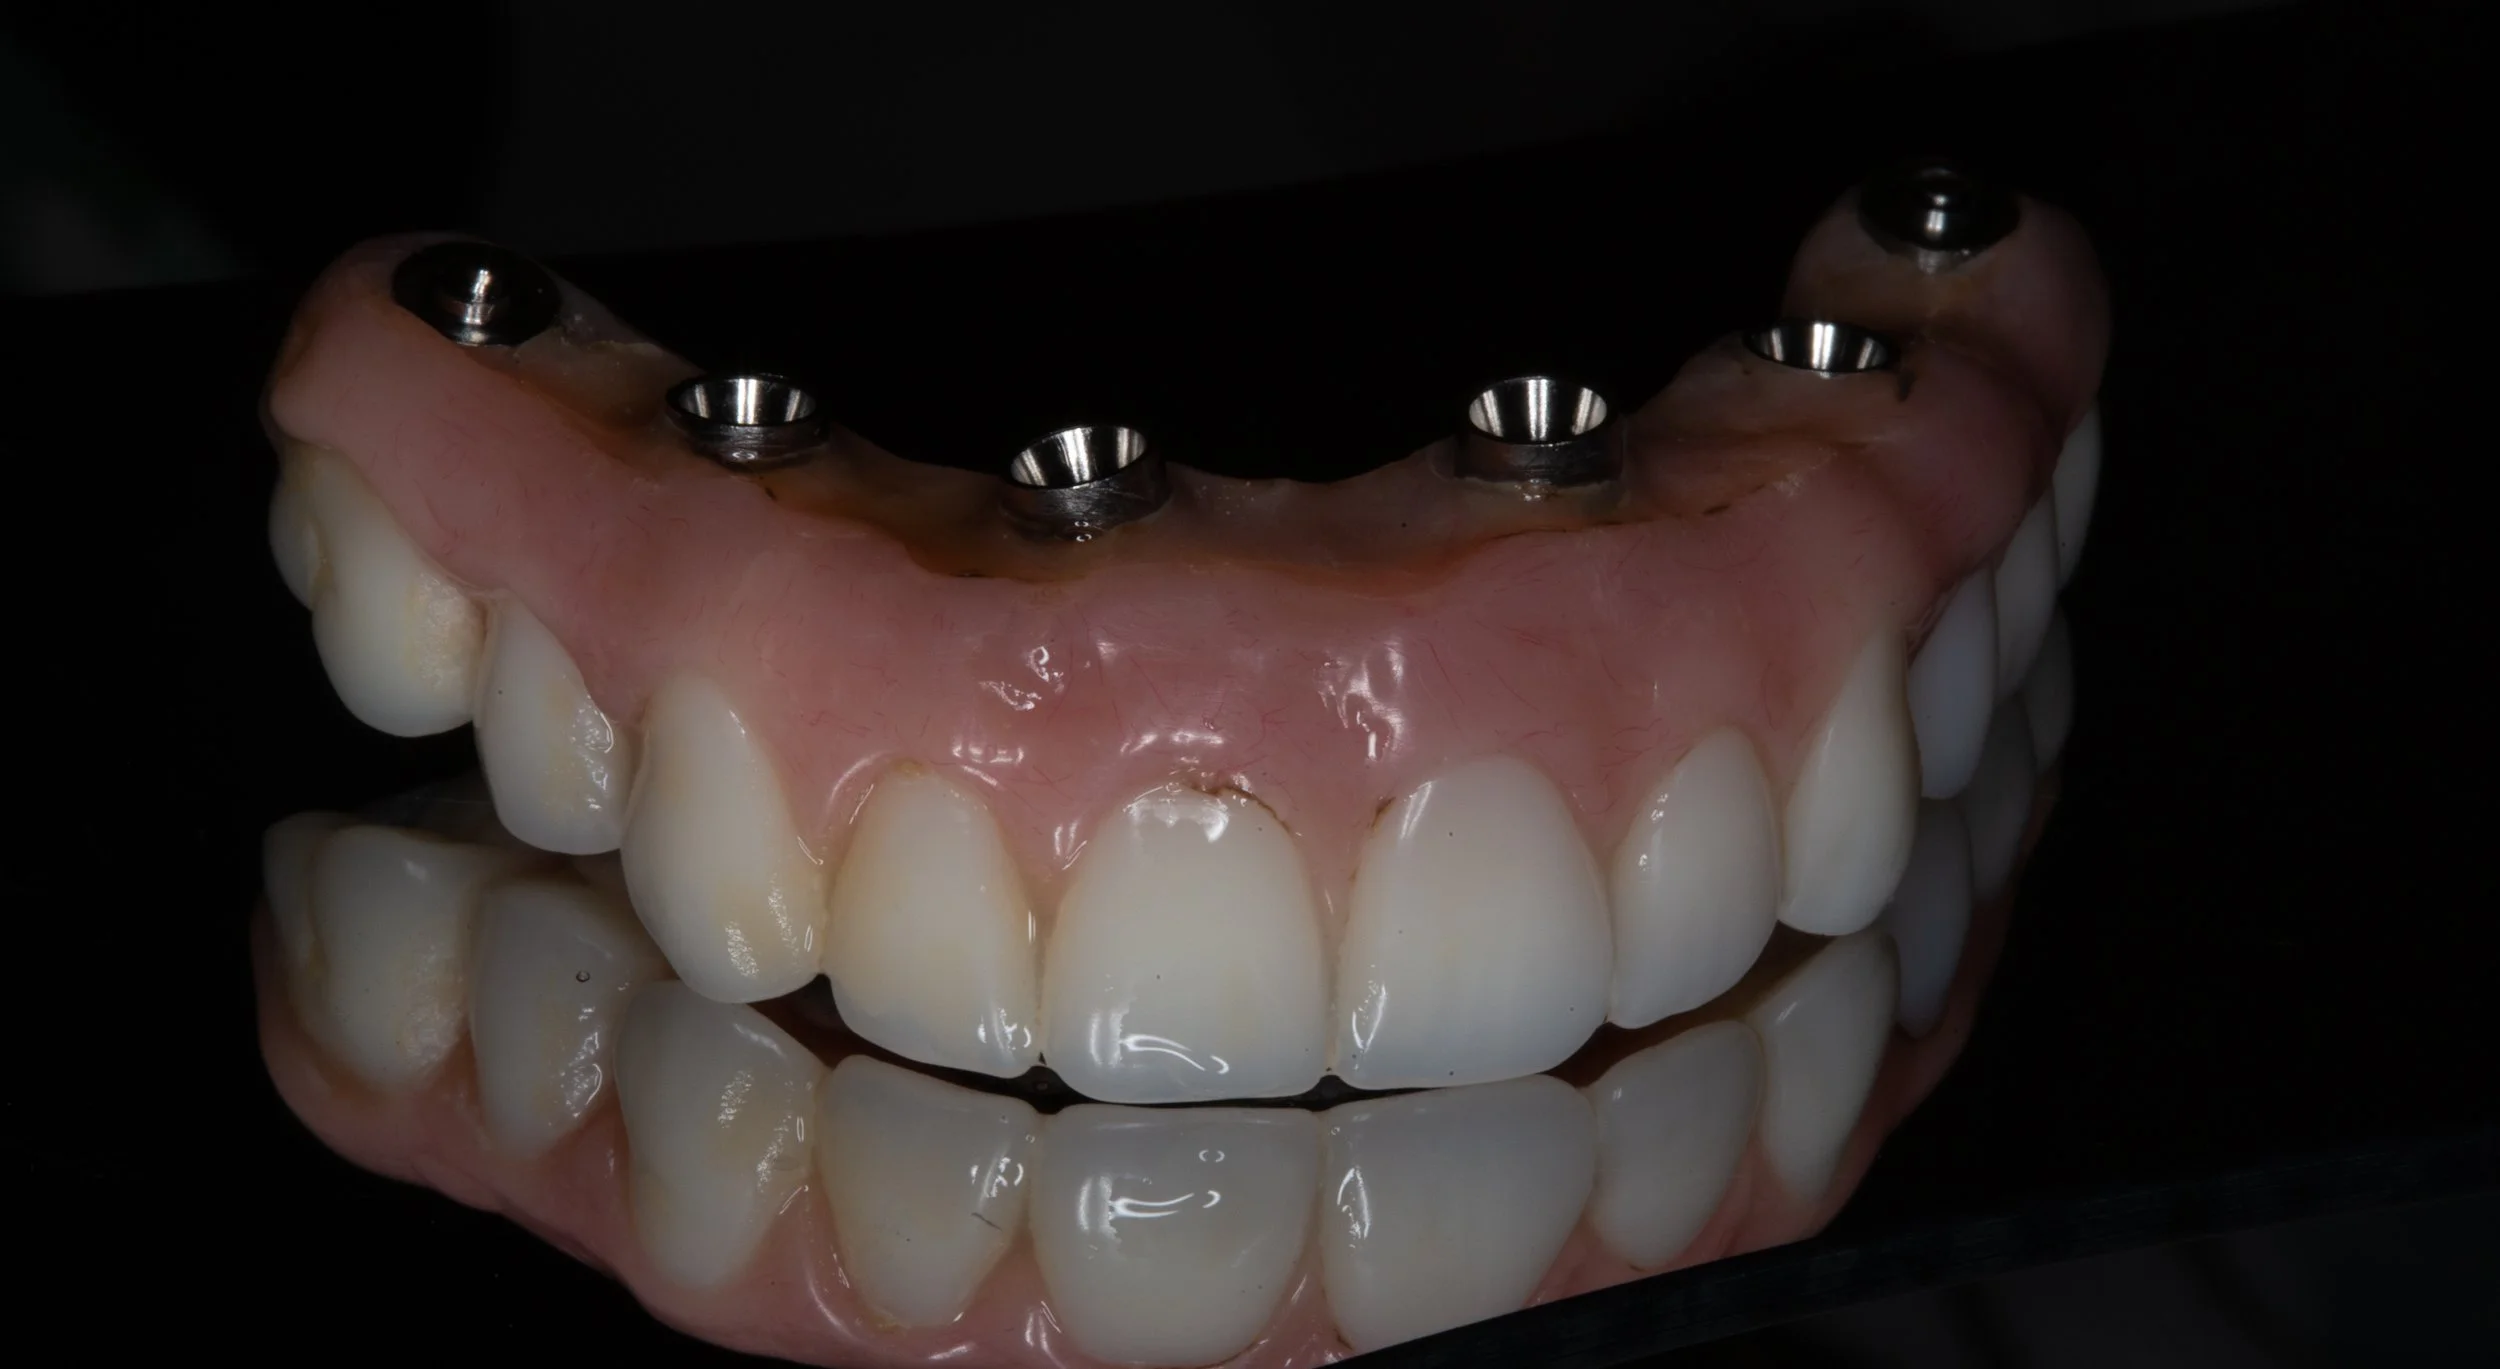

Replacing all of the upper or lower teeth with dental implants requires a high level of knowledge and coordination to ensure a successful outcome.